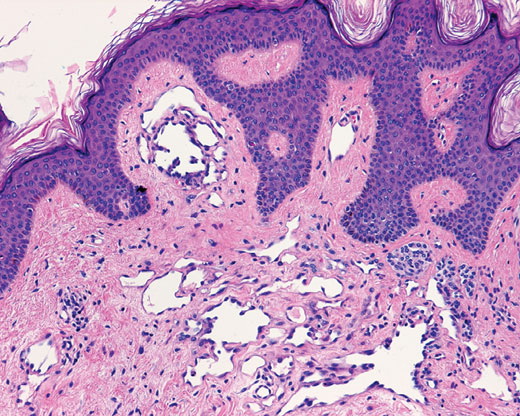

Atypical vascular proliferation =تكاثر وعائي لا نموذجي